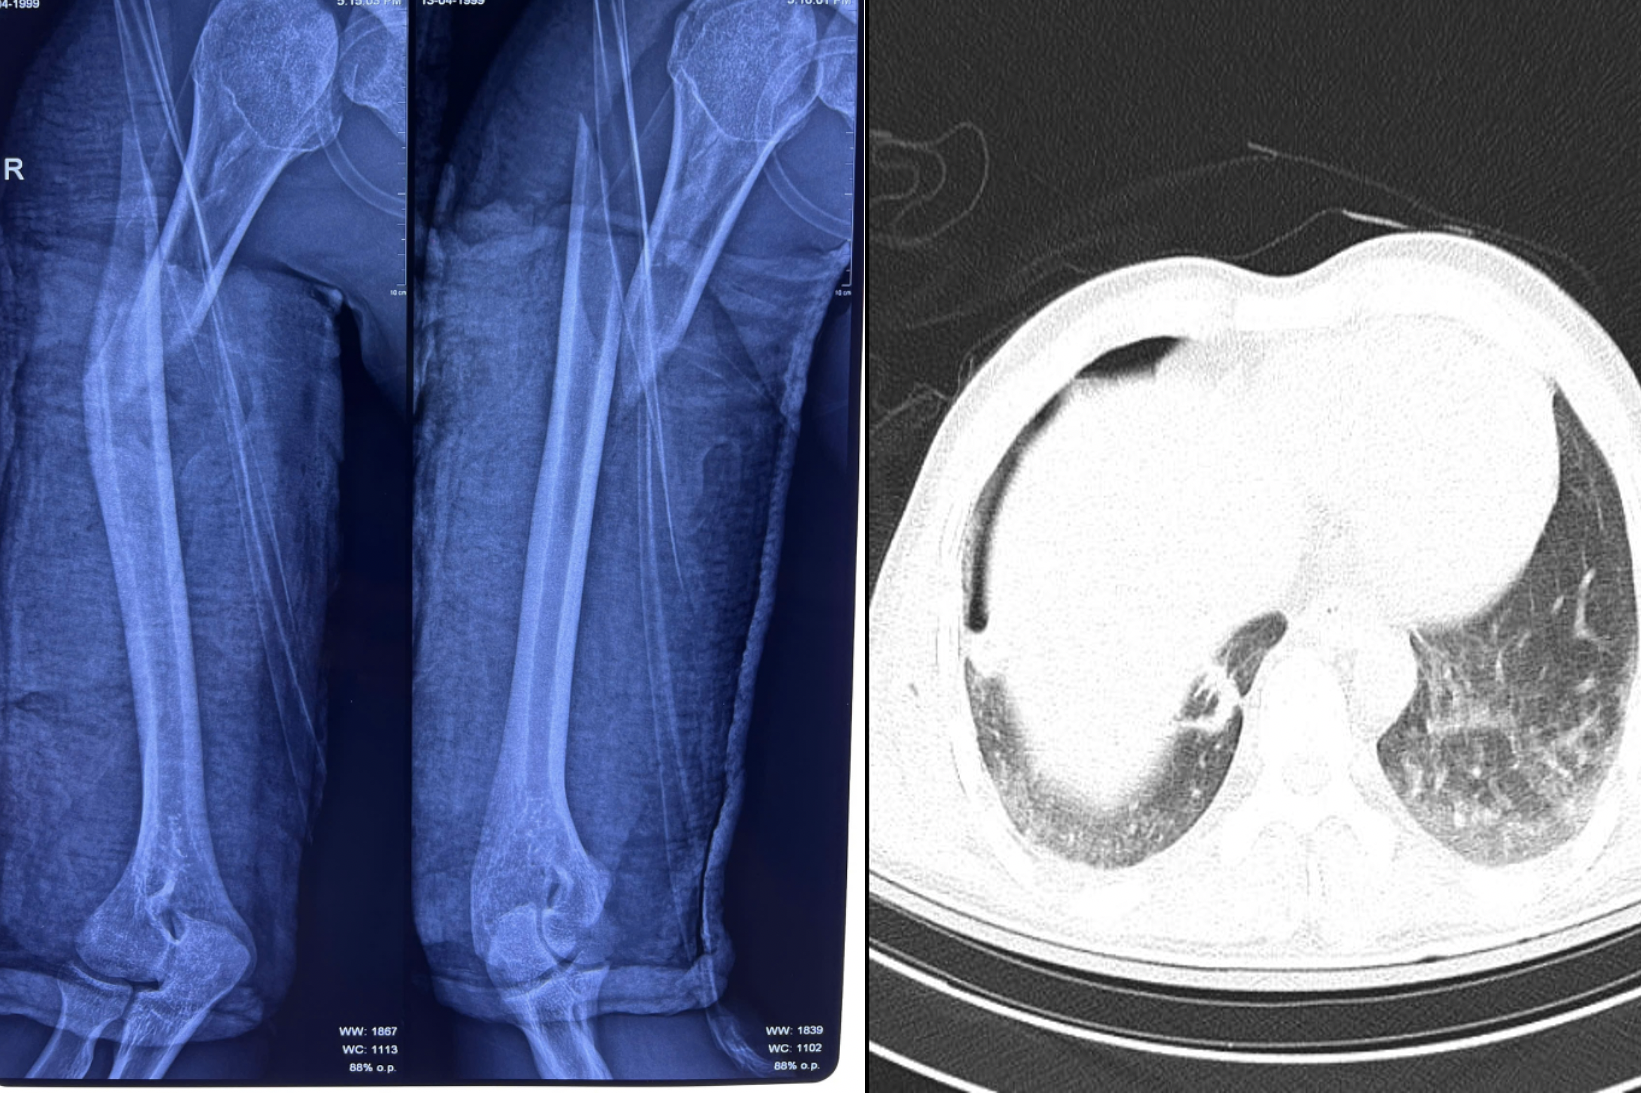

Kết quả chụp X-quang ngực tại giường cho thấy nam thanh niên bị tràn khí màng phổi phải do chấn thương dập phổi nặng, kèm gãy phức tạp đầu trên và gãy chéo dài 1/3 trên xương cánh tay phải”, BS.CKI Sơn Tấn Ngọc, khoa Chấn thương chỉnh hình cho biết.

Xương cánh tay phải của người bệnh bị gãy hoàn toàn, kèm dấu hiệu tràn khí màng phổi (Ảnh: BVCC).

Ê-kíp điều trị phân tích, gãy xương cánh tay là chấn thương thường gặp trong các vụ tai nạn. Nếu không được điều trị đúng cách, người bệnh có thể đối mặt với nhiều biến chứng nguy hiểm như nhiễm trùng, tổn thương thần kinh quay (ảnh hưởng khả năng vận động ngón tay), tổn thương mạch máu, chèn ép cơ.

PGS.TS.BS Vũ Hữu Vĩnh, Trưởng khoa Ngoại lồng ngực chia sẻ, với trường hợp này, trước tiên cần phải giữ được hơi thở và tính mạng của người bệnh, sau đó mới đến phần điều trị chấn thương tại cánh tay.

Liên tục trong 8 giờ, ê-kíp khoa Ngoại Lồng ngực đã tiến hành dẫn lưu màng phổi để phục hồi chức năng hô hấp cho người bệnh, giúp cải thiện suy hô hấp, ổn định nồng độ oxy máu về mức an toàn, sẵn sàng cho ca phẫu thuật kết hợp xương cánh tay.